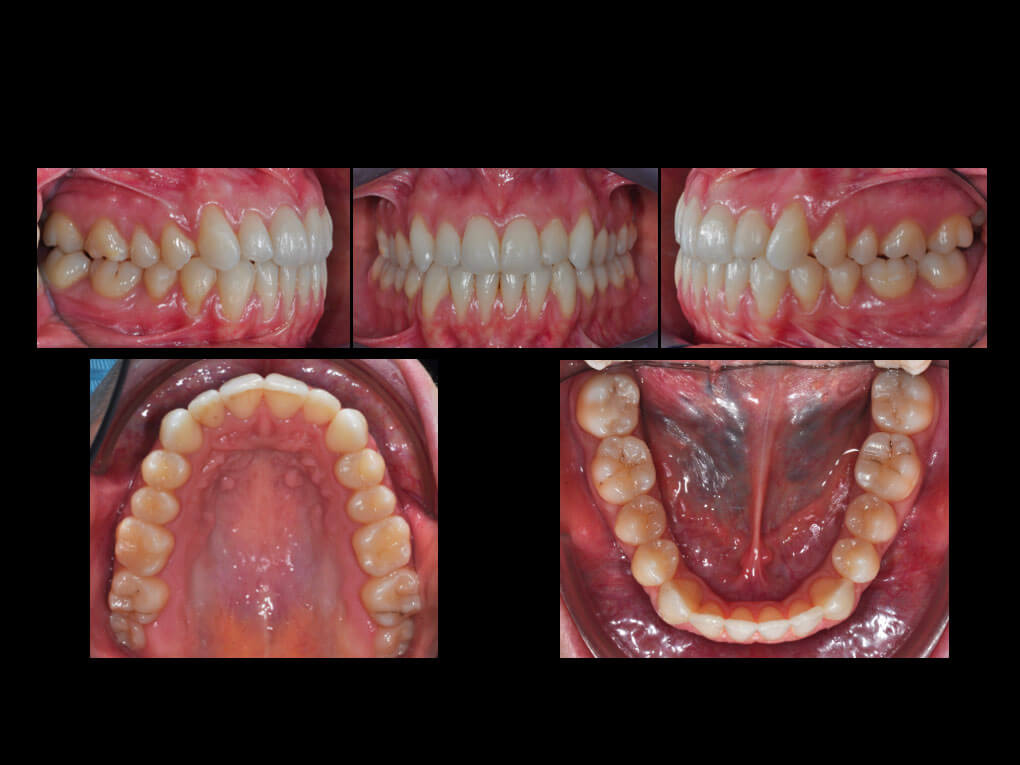

La paciente de 23 años presentaba una maloclusión de Clase III, una contracción esquelética del maxilar superior y una mordida cruzada posterior bilateral. Se observan diferentes recesiones a nivel de los sectores laterales y de los incisivos inferiores, que pueden remitir a un biotipo fino y a una encía especialmente delicada.

Cada alineador se utilizó durante siete días y, tras esta primera serie, se programó el acabado de otros cinco alineadores superiores e inferiores. Por lo tanto, el tratamiento global se completó en diez meses, de los que sólo seis se realizaron con alineadores F22. Clínicamente, el paciente muestra una clase 1 de relación molar y canina y diámetros transversales posteriores correctos. Las recesiones no empeoraron durante la terapia y ahora se pueden tratar con un enfoque quirúrgico de cobertura radicular.